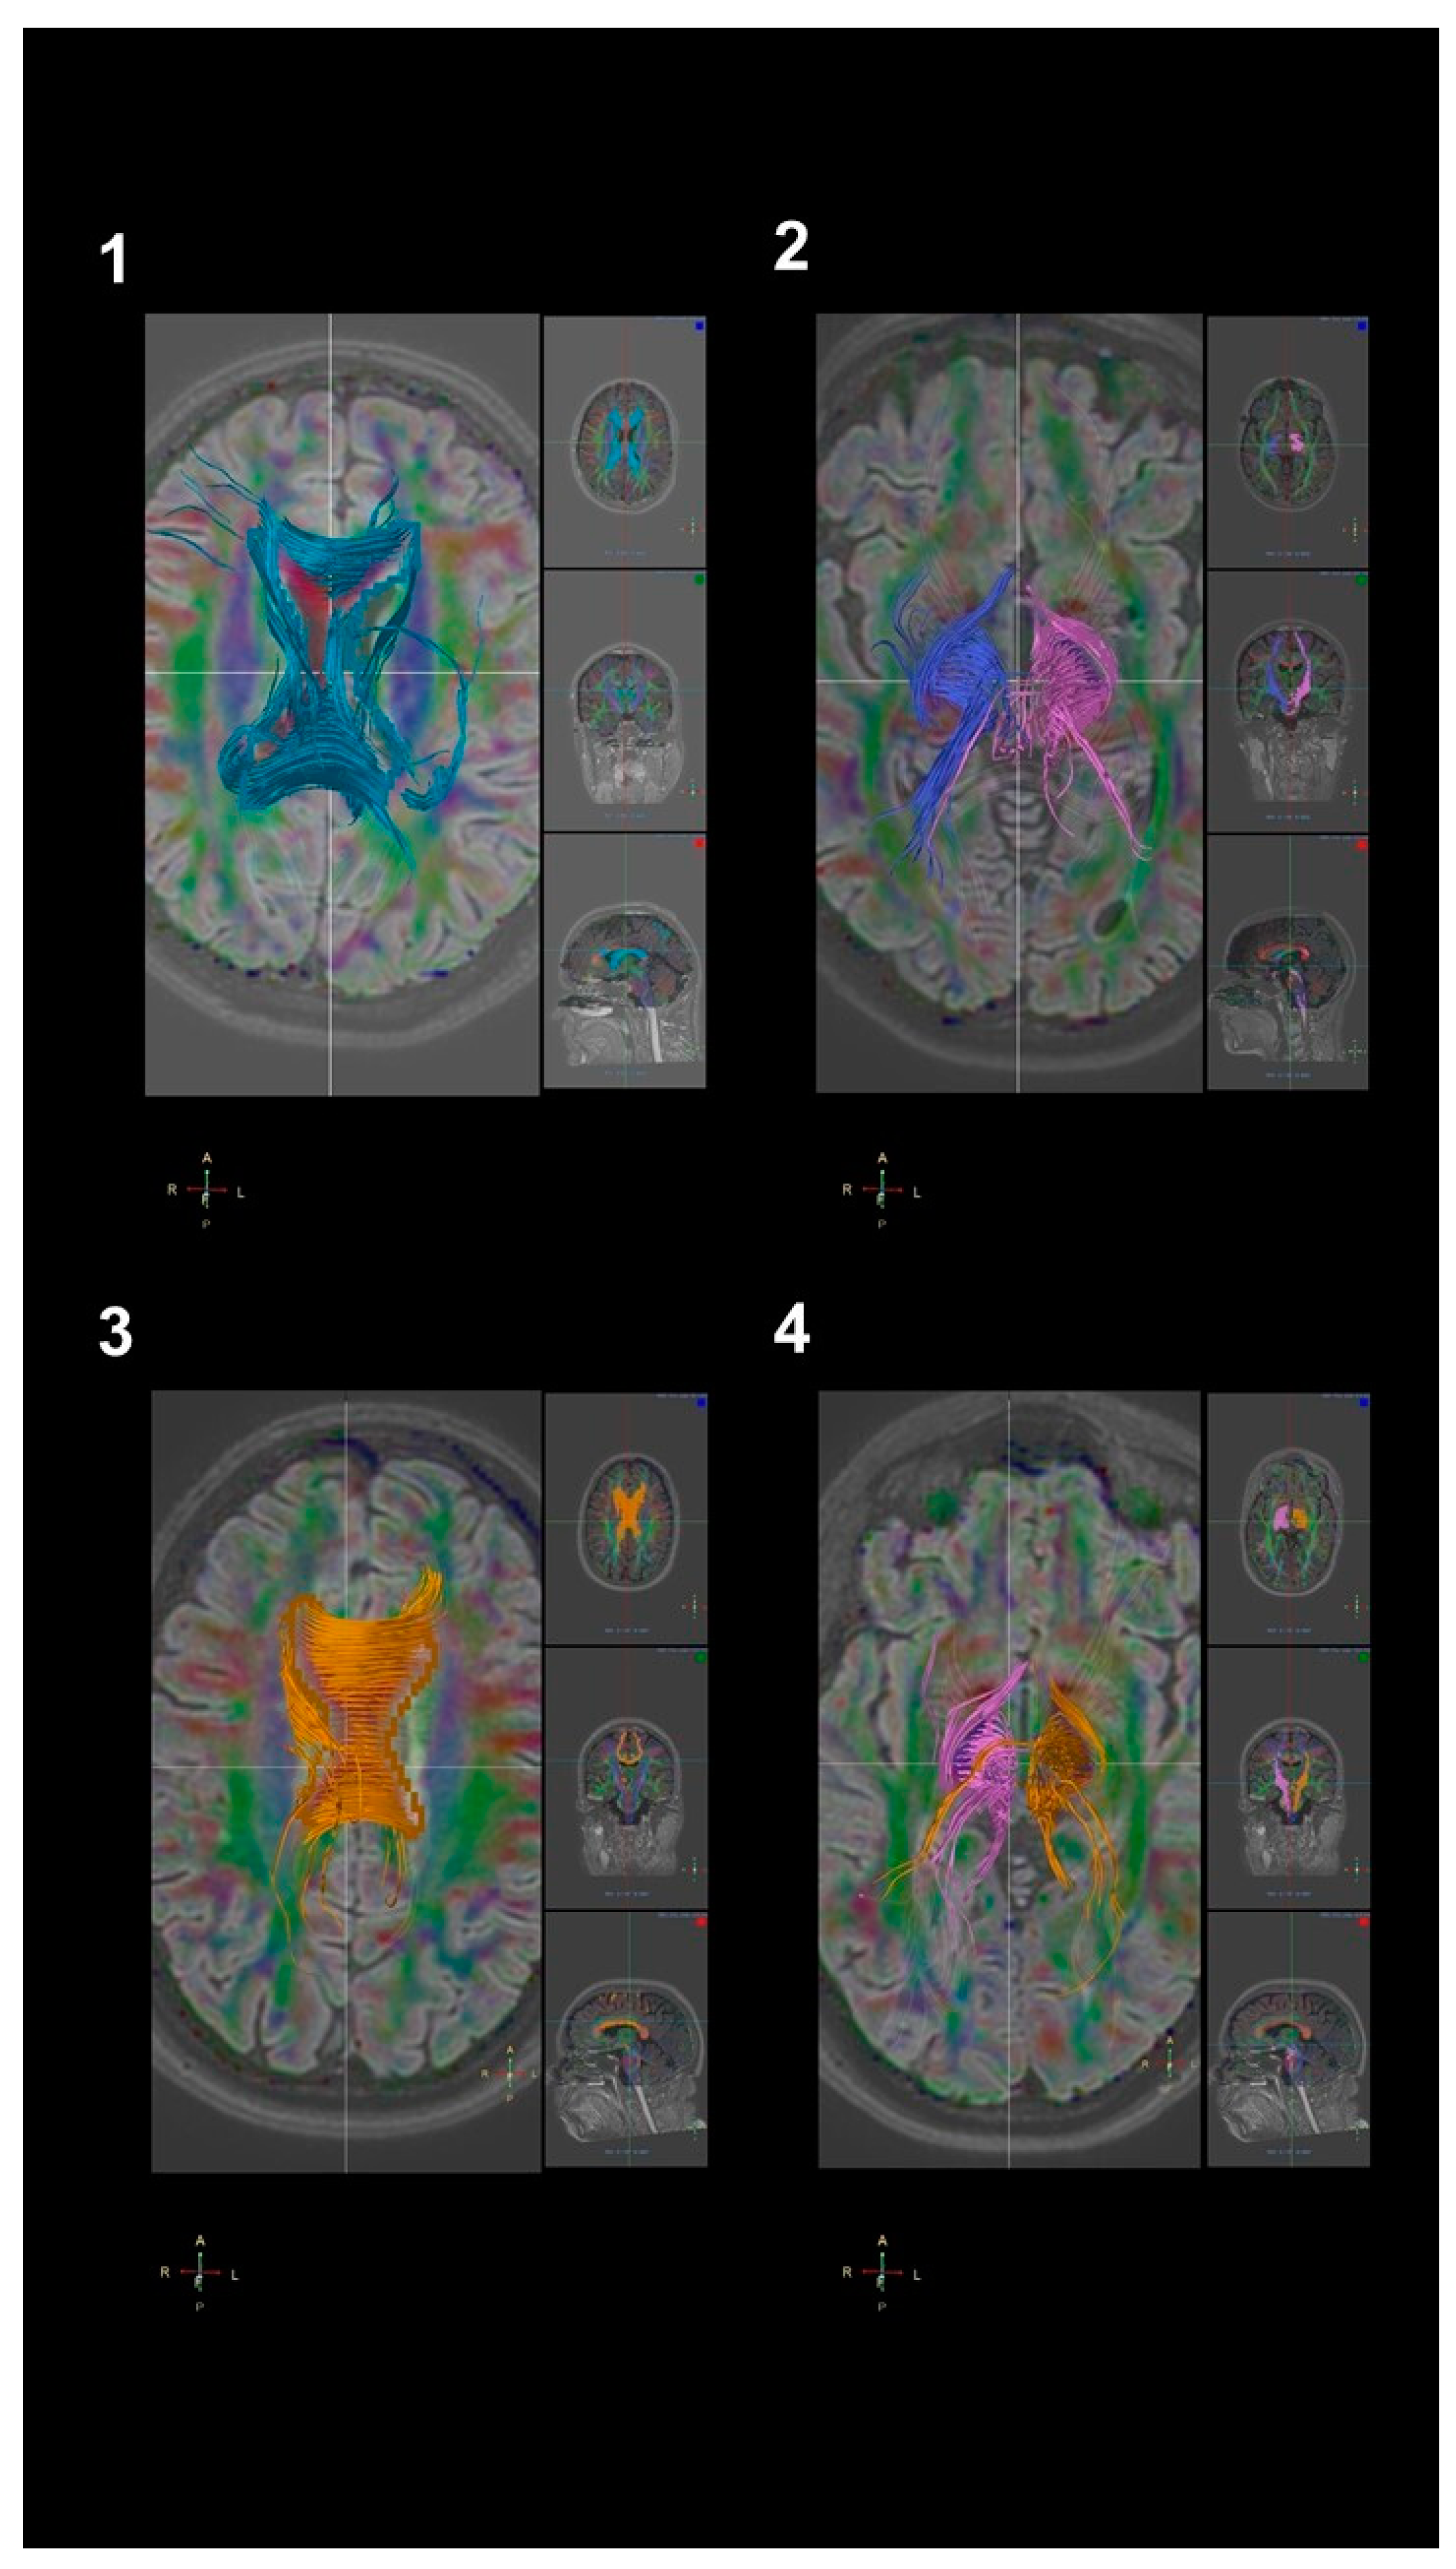

2.5. DTI Analysis

3.2. DTI Findings